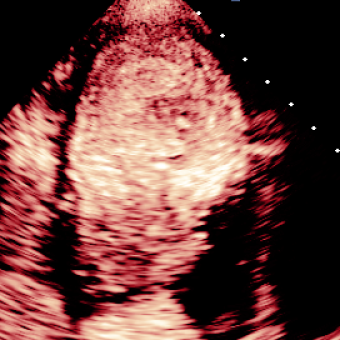

For variations caused by low quality images such as those of low resolution or significant artifacts, however, the unique ground truth may not be available. Take the myocardial segmentation task of Myocardial Contrast Echocardiography (MCE) as an example. An inter-observer experiment was conducted among five experienced cardiologists, and Fig. 1(a)(b) visualize the annotations of two images from three of these cardiologists. It can be seen that the labels by different cardiologists vary significantly, especially in locations where the intensity information of myocardium is very similar to the background. Table 1 shows the average Dice of the annotation of each cardiologist, using one of the others’ as the ground truth, over 180 images. We can observe that none of the Dice is above 0.9, some even under 0.8, confirming significant variations among the annotations. In this case, as the variations are caused by the image quality, even these cardiologists cannot tell which annotation is better than others, and a majority vote for ground truth would not make sense sometimes as can be seen in Fig. 1(c)(d). For this reason, we cannot obtain a unique ground truth in the evaluation process and the traditional metrics such as Dice and IoU cannot be used.